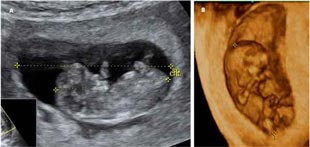

El desarrollo del bebé semana a semana continúa imparable. El cerebro del feto ha crecido mucho en la semana 10 de embarazo y por eso la parte superior de la cabeza sigue siendo mucho más grande en relación con el resto del cuerpo.

En la décima semana del desarrollo fetal, los párpados se han fusionado sobre los globos oculares y no volverán a abrirse hasta dentro de unas cuantas semanas, hacia la semana 24.

Ya se pueden ver con claridad las orejas -situadas muy abajo, casi a la altura de la boca-, y la punta de la nariz.

El feto de 10 semanas se mueve

El bebé ya cuenta con todas las articulaciones: codos, rodillas, muñecas y tobillo, y los dedos de manos y pies se han separado. Además puede moverse, gracias a que su sistema nervioso empieza a mandar las primeras señales. La madre aún no puede sentirlo porque es demasiado pequeño como para que sus movimientos puedan ser percibidos por ella, pero lo cierto es que flexiona sus bracitos y sus pequeñas piernas.